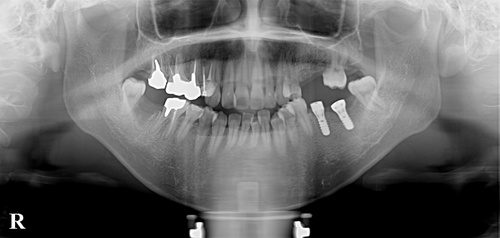

奥に2本のインプラントが入りました。

次回は、左の上にインプラントを2本入れる予定です。